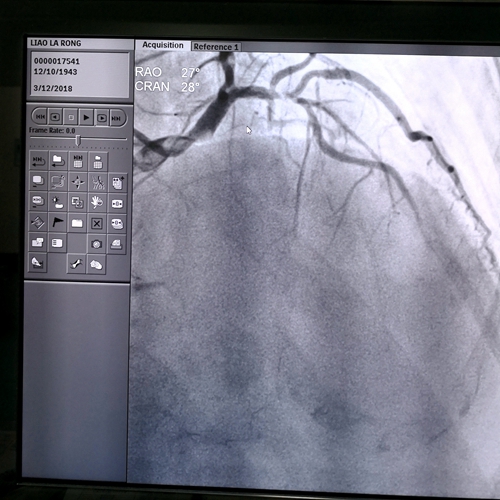

74岁的罗奶奶七个月前干重活和剧烈活动后就会出现上腹部一阵阵的绞痛,喝点水后,就会感觉舒服一些。 但是“腹痛”的情况在这几个月中反反复复出现,罗奶奶觉得情况有点不妙,便辗转了三家医院求诊且都...